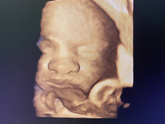

Сегодня ходила на третий скрининг, срок 30+5, малыш 1550 г, все в норме, головное предлежание. Шов состоятельный, но врач сказала, что тонкий (1,9-1,7). Абсолютно меня место шва не беспокоит (ттт). Блин, еще столько ходить, я не напрягаюсь, конечно, … Читать далее